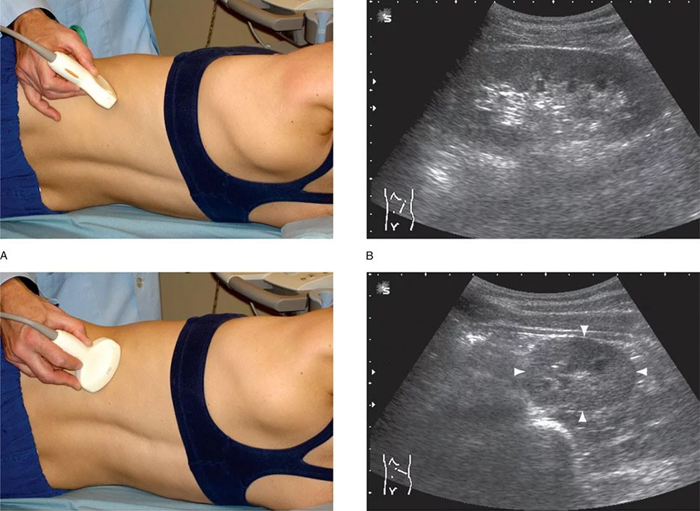

- Раздеваться не требуется, достаточно освободить тело выше пояса, приподняв одежду.

- Необходимо лечь на кушетку, повернуться на бок.

- Кожу смазывают гелем для устранения воздуха между телом и датчиком.

- К смазанному месту на коже прикладывают датчик и ждут появления изображения сосуда на мониторе.

- Датчик водят по телу в требуемом месте для тщательного рассмотрения всех искомых позиций.

- На все требующиеся области делают снимки, по завершении описывают в бланке анализа увиденное.

- Может потребоваться вдохнуть, а также поменять положение тела, если необходимо улучшить видимость найденных образований.

- Гель по завершении процедуры вытирают.